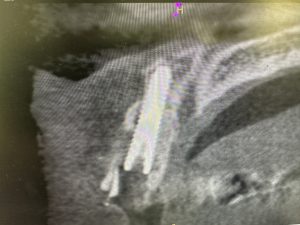

径3.5 長さ18ミリ、径4.0 長さ18ミリ

ISQ80台、ITV70〜80台👍

いつもフリーハンドだが、ドンビシャ!

顎骨形態が脳みそに染みこんでるからね

便利なCTソフト見てるからイメージが湧く